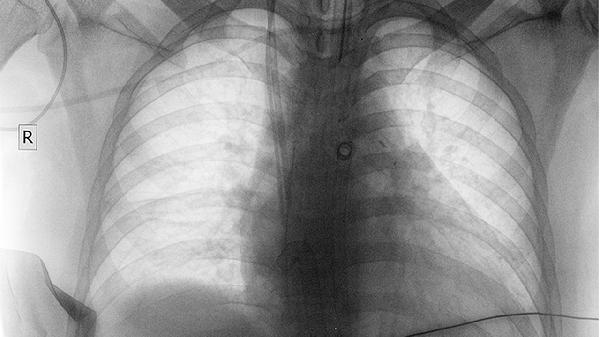

对于直径小于8毫米的良性结节,通常建议每6-12个月进行低剂量CT复查。随访期间需观察结节大小、形态及密度变化。磨玻璃样结节需更密切监测,部分可能随时间自行吸收。随访期间出现咳嗽加重或痰中带血应及时就诊。

直径超过15毫米的实性结节或随访中增大的结节,可能需胸腔镜下肺楔形切除术。高度怀疑恶性时需行肺段切除术或肺叶切除术。术后需进行病理检查明确性质,恶性肿瘤还需进一步综合治疗。微创手术创伤小但仍有气胸等并发症风险。